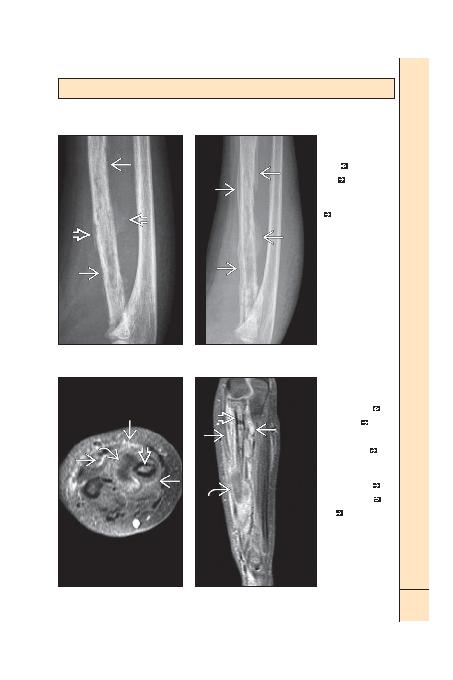

AKUT OSTEOMYELT: ÇOCUK

(Sol) ÖA radyografi yaygin

osteomiyeliti gösteriyor.

Radyusta boylu boyunca

immatür periosteal yeni kemik

yapimi

yaninda kortikal ve

medüller kemikte permeatif

yikim

izleniyor. (Sa) Ayni

hastanin takip amaciyla elde

olunmu ÖA radyografisi.

Periostit hem daha yaygin hem

de daha matürdür

. Kemik boyunca sklerozda

arti ve kortekste daha

belirginleme mevcuttur. Bu

kemik deiiklikler iyileme

sürecindeki yeni reaktif kemik

oluumunun sonucudur.

(Sol) lk deerlendirme

sirasinda elde olunmu

ayni hastanin aksiyel

T1A K+ MR kesiti hafif

ilik kontrastlanmasini

ve difüz yumuak doku

inflamasyonunu

gösteriyor.

Abse ile uyumlu olarak

periferal parlaklamasi diinda

kontrast tutmayan göreceli

hipointens bir odai

gösteriyor. (Sa) Ayni hastanin

sagital T1A K+ yb MR kesiti bu

planda daha iyi görüntülenen

kalinlami periostit boyunca

yaygin parlaklamayi

gösteriyor. Yine radyus iliinde

düzensiz parlaklama

ve

komu yumuak dokularda

abse

izleniyor. Abse

olduunun dorulanmasi

için bu odakta siviya-duyarli

sekanslarda yüksek sinyal

olmalidir. Eer bu odak siviya-

duyarli bir sekansta hipointens

özelliini koruyor ise yaygin

enfeksiyona nadiren elik

eden devitalize (devaskülarize)

dokuyu temsil ediyor olmasi

daha olasidir.

lk 7-10 günlerde uygun

tedaviye ramen radyografik

deiikliklerde arti var gibi

görülebilir. Burada izlenen

deiikliklerin olumasi için

2 hafta ve üzeri süreli uygun

tedavi gerekebilir.